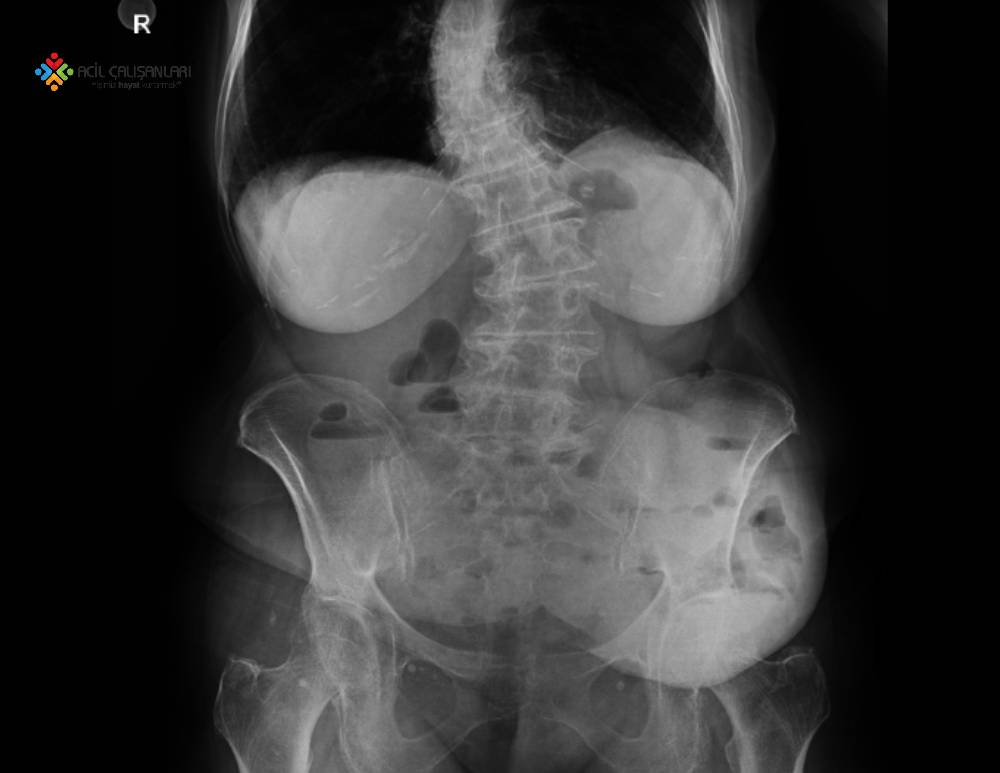

66 yaş bayan hasta acil servise karın ağrısı nedeniyle getiriliyor. Öyküsünde sabah 4 den beri epigastrik bölgede şiddetli ağrısının olduğunu, akşam yemeğinde etli bir yemek yediğini ve iki gündür dışkılayamadığını söylüyor. Hasta acil sarı alan doktoru tarafından değerlendiriyor; GKS:15 Genel Durumu: İyi Bilinç: Açık Oryente Koopere SpO2: 98 Ateş: 36,5 °C Nabız: 105 atım/dk SS: 14/dk Ta: 120/80 mmHg olarak saptanıyor. Fizik muayenede epigastrik bölgede hassasiyet, defans yok rebound yok ve diğer sistem muayeneleri doğal olarak değerlendiriliyor. Hastanın laboratuvar incelemesinde; Venöz Kan Gazında pH: 7.36, pO2: 37.2 mmHg, pCO2: 23.5 mmHg, HCO3: 22.7 mEq/ dL, BE: -2 Biyokimyada: sodyum 138 mEq/L, potasyum 3,8 mEq/L, klorür 97 mEq/L, bikarbonat 10 mEq/L üre:46 mg/dl, kreatinin:1.3 mg/ dl, lipaz 1000 IU/L , amilaz 3000 IU/L olarak sonuçlanıyor. Hemogramda: beyaz küre sayısı 16.700/mm3, hemoglobin: 15.5gr/dl ve diğer kan laboratuvar değerleri ve idrar tahlilinde normal saptanıyor ve hastaya ADBG çekiliyor Bundan sonraki yaklaşımda aşamalarıyla doğru olan seçenek hangisidir?

Serum amilaz ve lipaz testleri AP tanısı amacıyla en çok kullanılan biyokimyasal belirteçlerdir. Bu testler tipik olarak pankreatik enflamasyon esnasında yükselirler. Fakat yüksek amilaz ve lipaz değerlerinin özgüllüğü ve duyarlılığı yetersiz olduğu için tanıda altın standart değildir. Normal seviyedeki amilaz değerleri AP tanısını dışlamada yeterince duyarlı değildir. Serum amilaz veya lipaz değerlerinin normal seviyesinin üst sınırdan üç kat daha (hastamızda lipaz 1000 IU/L , amilaz 3000 IU/L) yüksek ölçülmesi karın ağrılı hastalarda AP tanısını destekler niteliktedir.